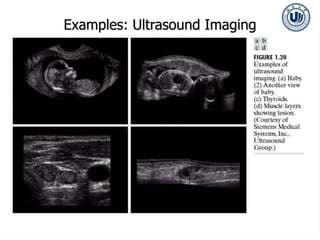

Examples: Ultrasound Imaging